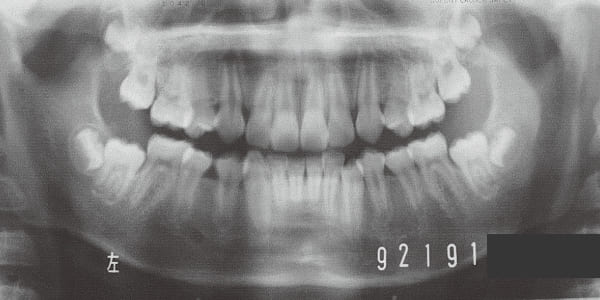

Age at initial visit : 7 y 7 m, male /Protruding upper bite. Open bite. Receding lower jaw. Protruding dual dentition.

The Class II condition is pronounced, with a significant overjet of 12.5 mm(3). Although the teeth size are large, crowding is relatively mild. The maxillofacial structure has good depth and a robust bone framework(5). The mandible itself is solid , robust gonial angle, but there is significant anterior-posterior displacement relative to the maxilla(ANB 10.0°). While there is no confirmed history of thumb-sucking or similar habits, the lower lip is already pushing up against the maxillary incisors. The cause of this condition is unknown.